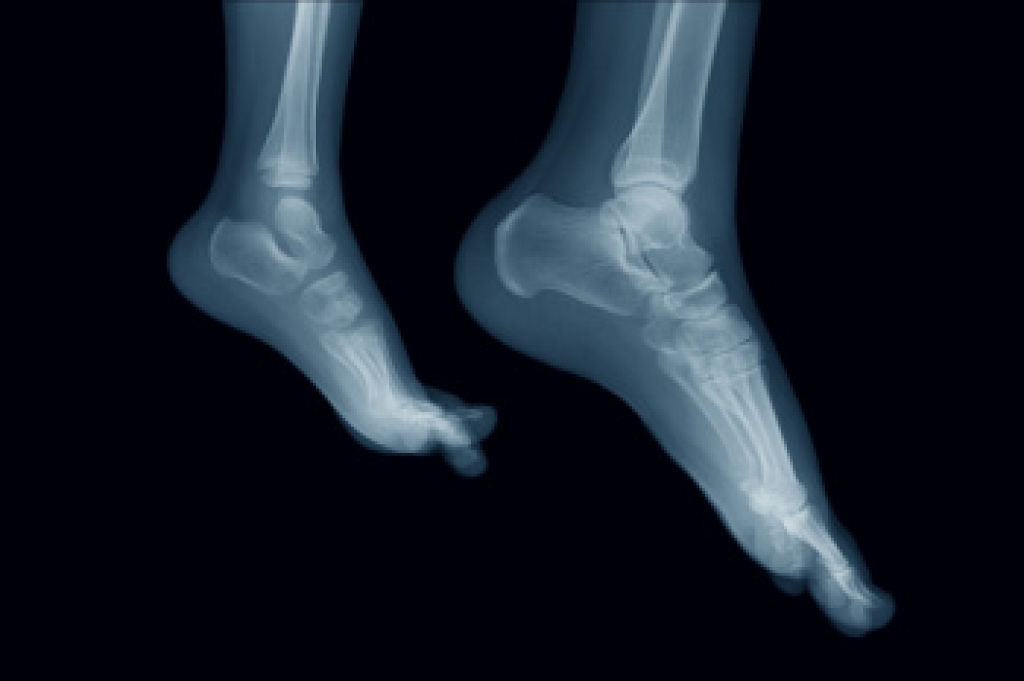

Stress fractures occur in the foot and ankle when muscles in these areas weaken from too much or too little use. The feet and ankles then lose support when walking or running from the impact of the ground. Since there is no protection, the bones receive the full impact of each step. Stress on the feet can cause cracks to form in the bones, thus creating stress fractures.

Pain from the fractures occur in the area of the fractures and can be constant or intermittent. It will often cause sharp or dull pain with swelling and tenderness. Engaging in any kind of activity which involves high impact will aggravate pain.